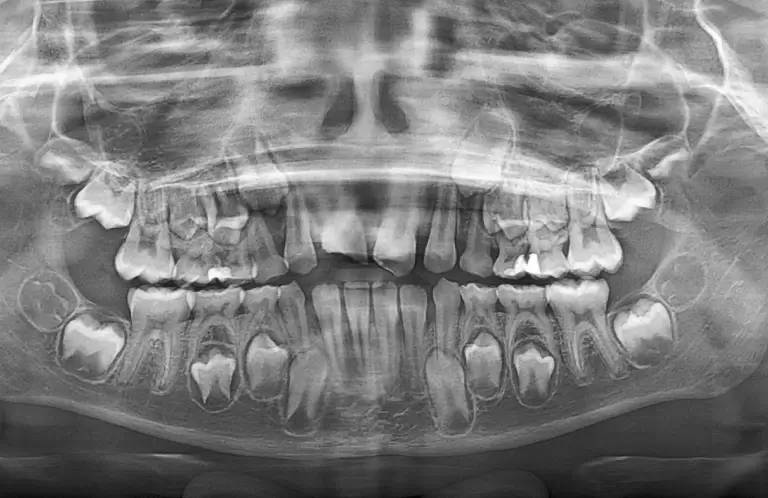

- Pantomogram – zdjęcie rentgenowskie, które obejmuje całą szczękę i żuchwę, idealne do diagnostyki problemów z zębami, kośćmi oraz przyzębiem.